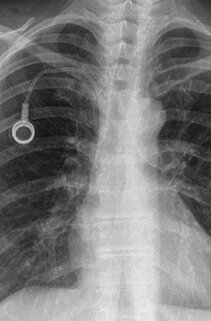

Patienten, die an bösartigen Tumoren erkrankt sind, benötigen häufig eine Chemotherapie, eine intensivierte Schmerztherapie oder eine parenterale Ernährung - die Durchführbarkeit und Handhabung dieser Therapien kann durch Anlage eines Ports oft wesentlich vereinfacht werden. Die Portambulanz der Klink für Thoraxchirurgie Freiburg führt Portimplantationen bei Patienten durch, die sich in ambulanter oder stationärer Behandlung befinden. Ziel ist es dabei, den Eingriff baldmöglichst und mit wenig organisatorischem Aufwand durchzuführen.

Die Freiburger Portambulanz bietet regelmäßige Termine für eine Portanlage. Jeden Dienstag und Freitag führen Fachärzte die Implantationen im chirurgischen Ambulanz OP durch, dadurch ist das Einsetzen eines Portkatheters schon innerhalb weniger Tage möglich. Die Abteilung ist dabei auch auf besonders dringende Fälle eingestellt. Meist gelingt es dem Team, einen Termin für den wichtigen Eingriff auch kurzfristig zu ermöglichen. Die thoraxchirurgische Portambulanz wird durch Herr Dr. Osei-Agyemang sowie Frau Dr. Moneke betreut. Die beiden Fachärzte können Sie bei einer anstehenden Portanlage oder Fragen gerne kontaktieren.